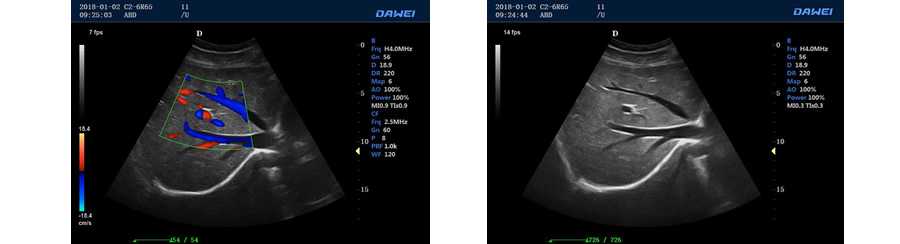

PIP智能畫中畫成像模式

●彩色多普勒血流成像單元

●方向性彩色能量多普勒成像單元

多普勒模式

具有PW脈沖波多普勒和CW連續(xù)波多普勒